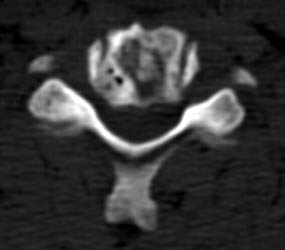

The axial images, and the sagittal reconstructions (not

shown) show some central lucency in the region of graft placement,

suggesting partial resorption of the graft material. |